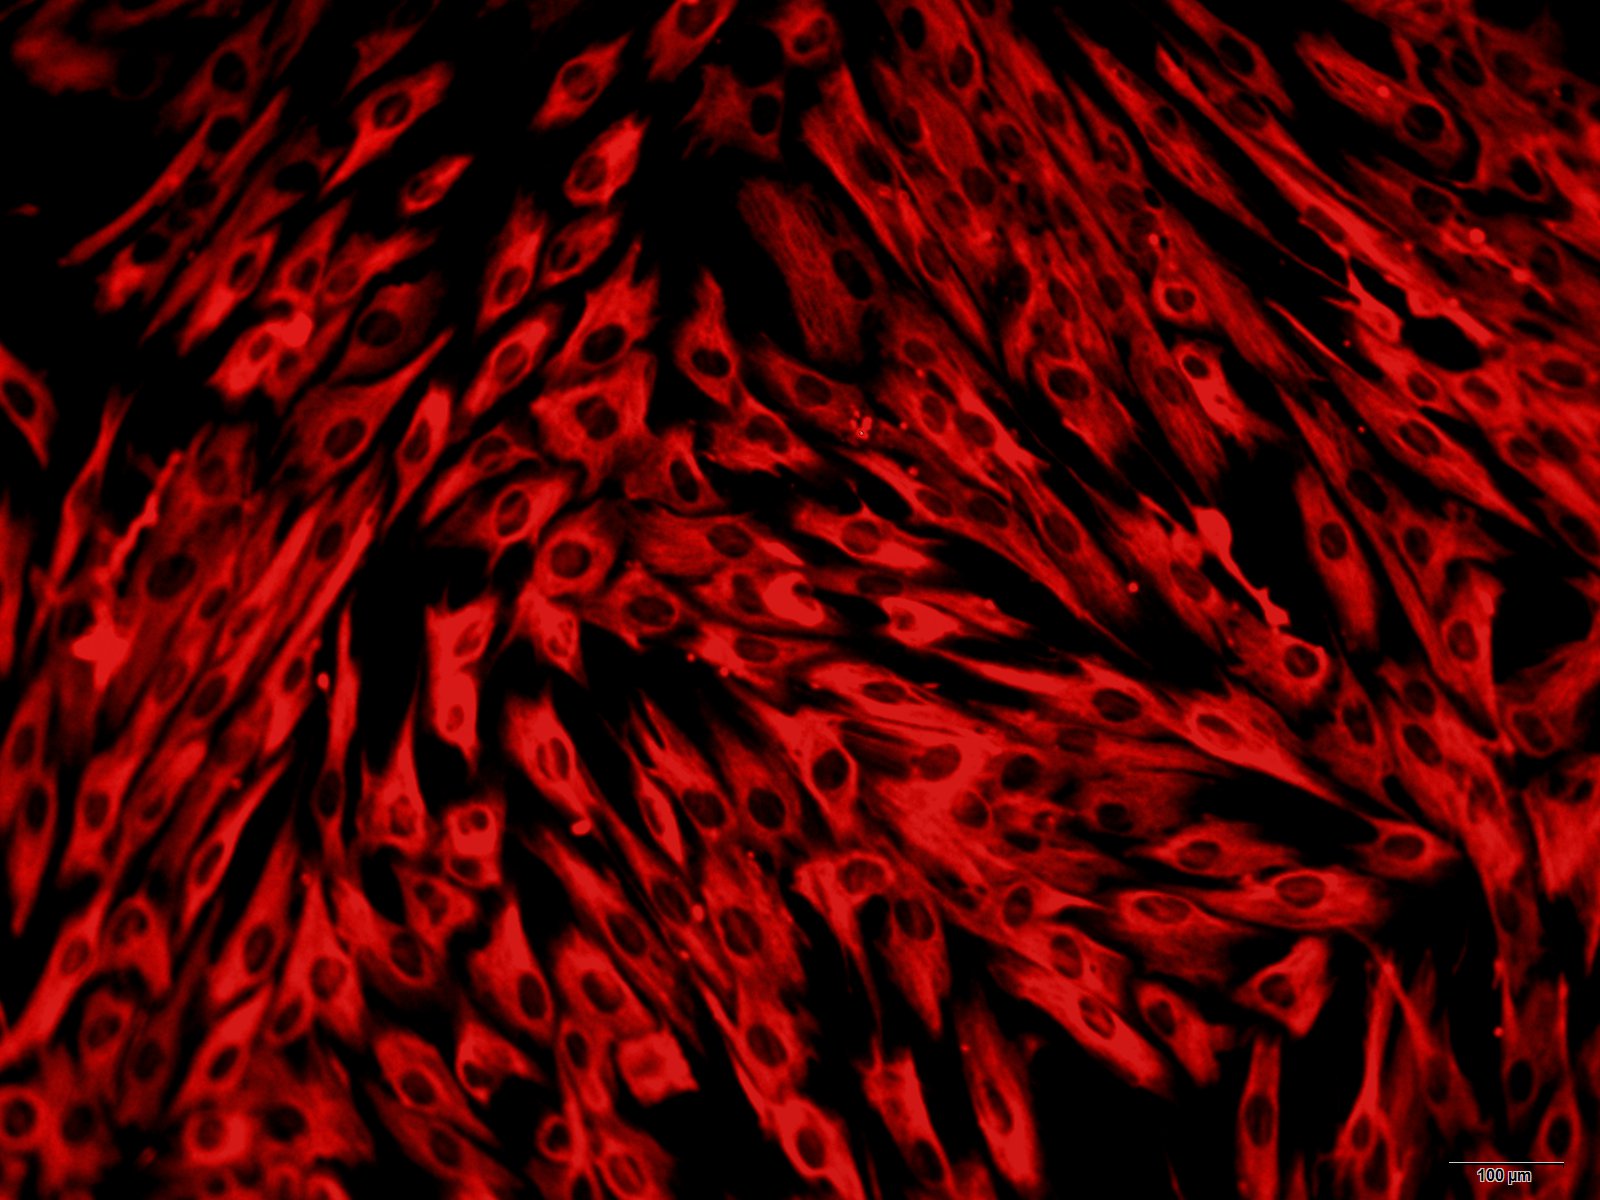

大鼠视网膜微血管内皮细胞

大鼠视网膜微血管内皮细胞(原代细胞)